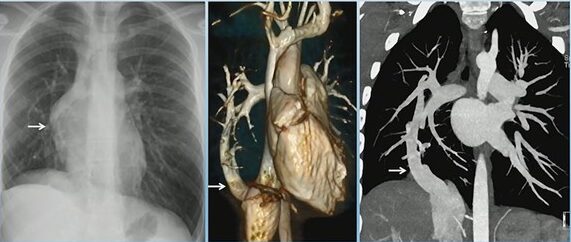

True vs. False Lumen in Acute Aortic Dissection

Look for the beak sign and larger caliber to ID the false; check the arch “wraparound” and calcification patterns for truth.